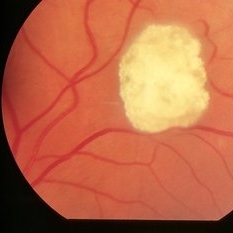

Best Disease

Oct 9 2012 by Alan D. Letson, MD

"egg Yolk" vitelliform lesion

Photographer: Beverly Radcliffe

Condition/keywords: Best disease